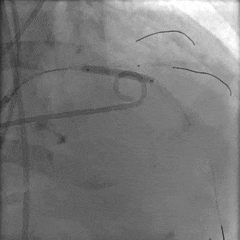

输送器过弓

snare辅助下跨瓣